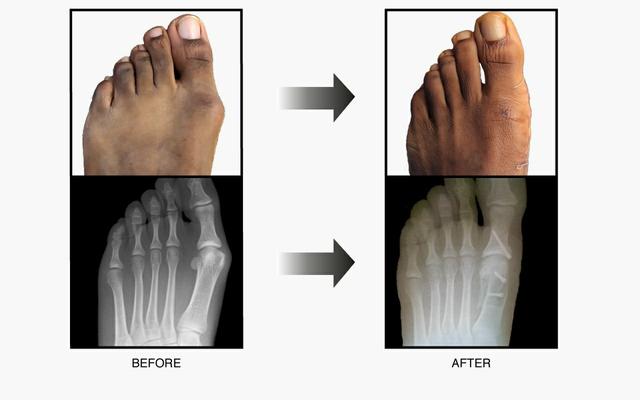

难看疼痛穿不了鞋折磨人的大脚骨外翻该怎样治疗

图片尺寸500x520